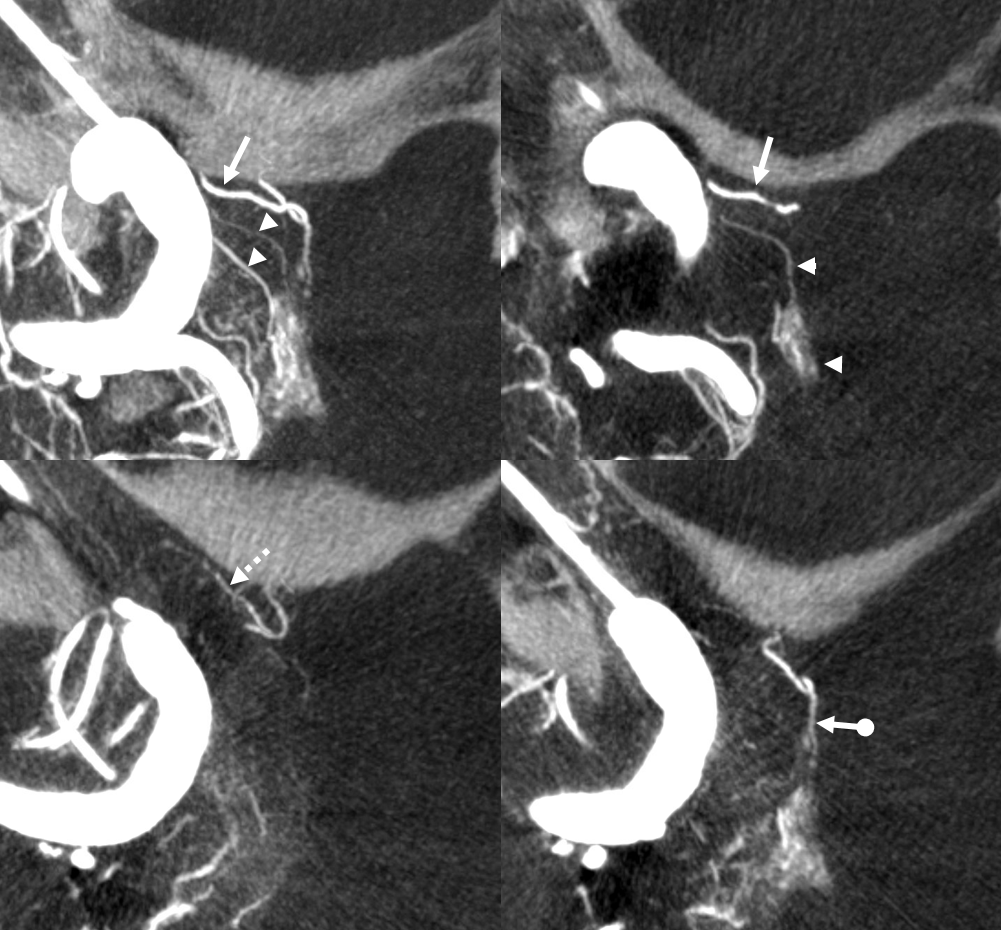

If you want to see hypophyseal arteries, do some high res DYNA of VASO imaging. Because of superimposition over the carotid in lateral views, again, its hard to see. Below is an example of why this artery, always there (always, yes! — occlusion is pathologic always such as athero) depends on technique

Stereos and MIPs. Both superior and inferior hypophyseals are well seen. The superior hypophyseal, despite being invisible on standard issue views, is quite large, even having two branches to the hypophysis.

Case courtesy Dr. Eytan Raz — here is a beautiful example of a very dominant superior hypophyseal artery (arrow) supplying the posterior hypophysis (arrowhead), with a correspondingly small inferior hypophyseal contribution from the MHT (dashed arrow)

Cross eye stereo

View from the back — again small inferior hypophyseal, big superior hypophyseal — balance again… See the beautiful vascular ring of the posterior pituitary — the connecting it with the contralateral side

MIP image shows the sella nicely — and helps prove its posterior pituitary

Of course, there is an aneurysm here — the branch point camp would point out how this larger than usual branch is a setup for aneurysmal formation. Naturally…